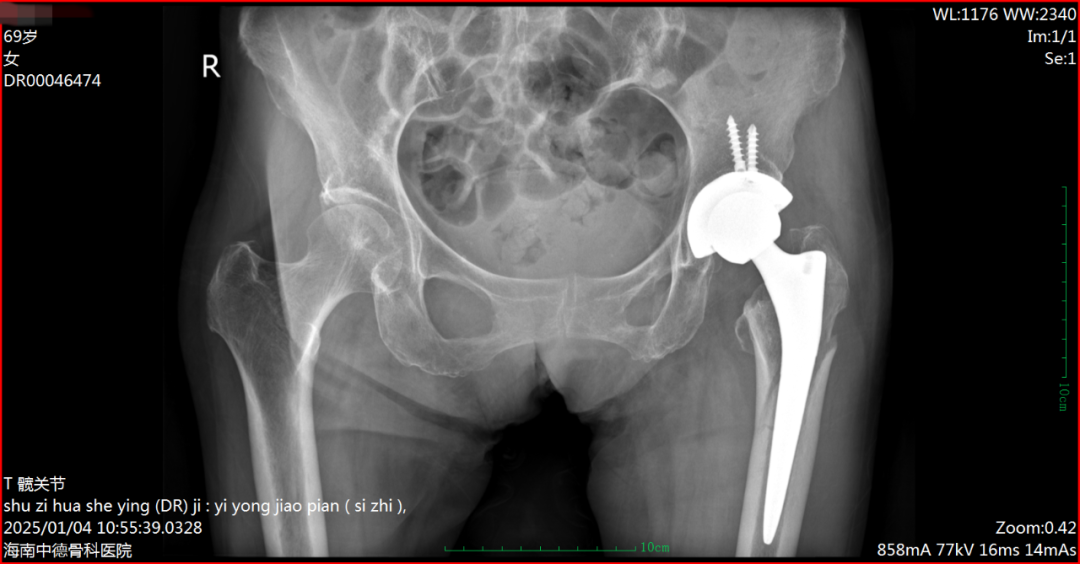

术前DR片(69岁张阿姨)

无独有偶,现年69岁的张阿姨,2年前在当地医院置换左侧髋关节,近日因在家踩滑摔倒致左大腿疼痛、肿胀伴活动受限,入院诊断:左股骨近端假体周围骨折、骨质疏松。